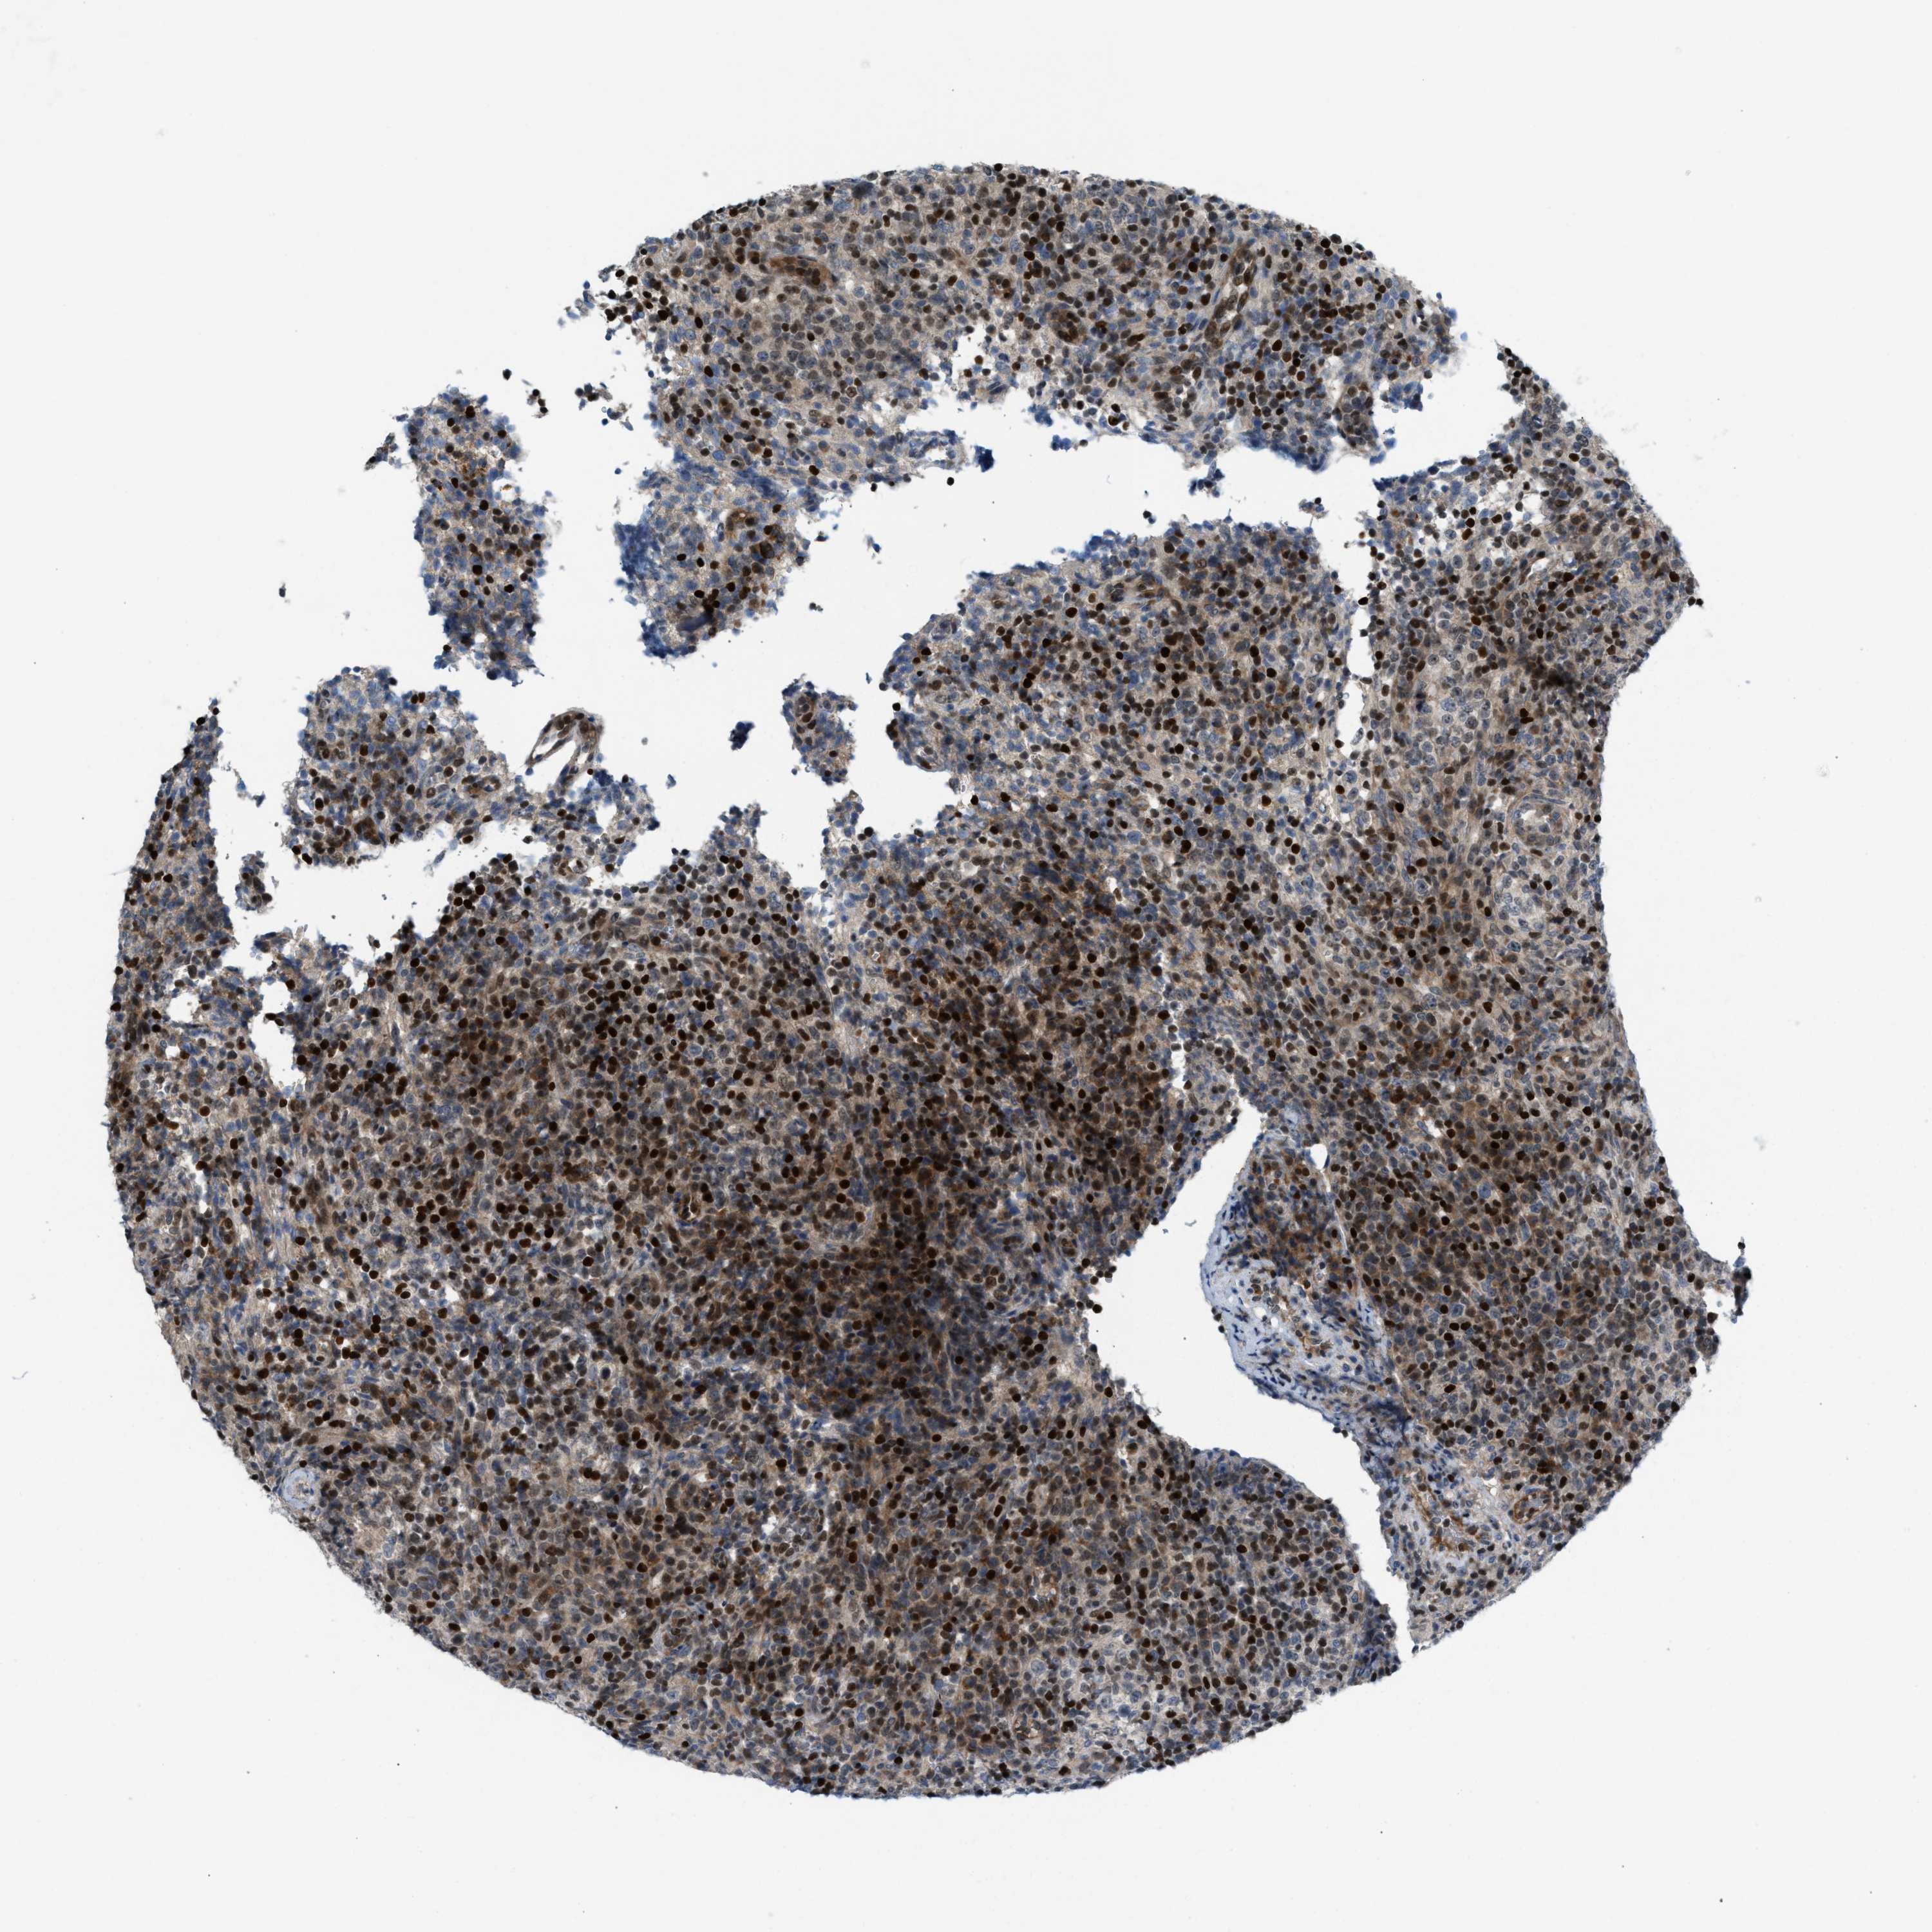

LYMPHOMA - Protein expressioni

A mouse-over function shows sample information and annotation data. Click on an image to view it in a full screen mode. Samples can be filtered based on level of antibody staining by selecting one or several of the following categories: high, medium, low and not detected. The assay and annotation is described here.

Antibody stainingi

Antibody staining in the annotated cell types in the current human tissue is reported as not detected, low, medium, or high, based on conventional immunohistochemistry profiling in selected tissues. This score is based on the combination of the staining intensity and fraction of stained cells.

Each image is clickable and will lead to virtual microscopy that enables deeper exploration of all samples and also displays staining intensity scores, fraction scores and subcellular localization as well as patient and tissue information for each sample.

Antibody HPA021309

Antibody HPA022255

Staining

High

Medium

Low

Not detected

Intensity

Strong

Moderate

Weak

Negative

Quantity

>75%

75%-25%

<25%

None

Location

Nuclear

Cytoplasmic/membranous

Cytoplasmic/membranous,nuclear

Hodgkin's disease, NOS

Malignant lymphoma, non-Hodgkin's type, High grade

Malignant lymphoma, non-Hodgkin's type, Low grade